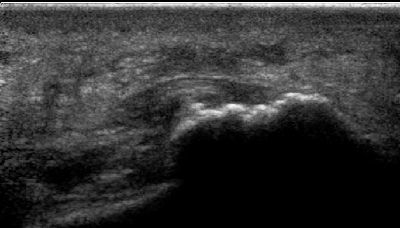

Becco osteofitico della 1a articolazione metatarso-falangea becco osteofitico prima metatarso-falangea